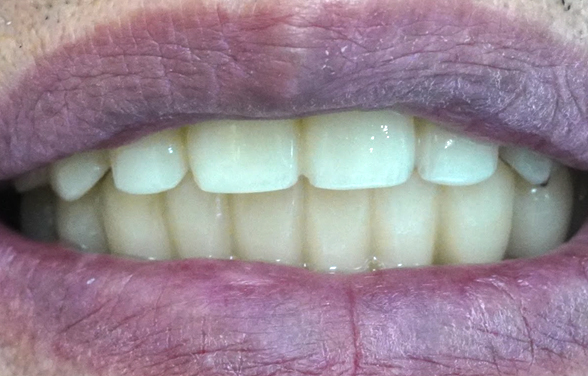

전체 임플란트, 단순히 치아가 생기는

것뿐만 아니라 예뻐져야 합니다.

치료 전후를 미리 예상해볼 수 있고, 기능적/심미적 개선을

통해 드라마틱한 얼굴 변화를 얻을 수 있습니다.